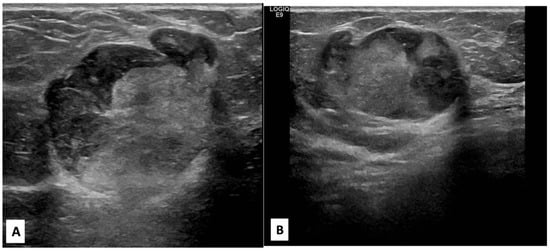

There was no indication of inflammation or swelling in either breast. A mammogram showed a large fat-containing oval-shaped lump with a circumscribed outline, and the mass in the upper outer quadrant of the right breast was approximately 9 cm from the nipple and measured 3 × 3.5 cm2 (Figure 2). However, mammography of the left breast showed nothing out of the ordinary. The subsequently targeted ultrasonography (US) revealed a heterogeneous isoechoic irregularly shaped solid mass that measured 3.3 × 3 cm2 and had eccentric cystic foci placed at the 9 o’clock position and approximately 8 cm away from the nipple (Figure 3). Differential diagnoses include phyllode tumor (PT) in addition to liposarcoma. The patient sought treatment at a tertiary hospital, where she underwent a right breast biopsy, and based on the findings of that procedure, a right lumpectomy without an axillary dissection was conducted. When seen under a microscope, the tumor was found to contain mature adipocytes, atypical spindle cells, and multivacuolated lipoblasts. All of these cell types were discovered to be embedded in a loose myxoid to fibrous stroma within the tumor itself. This information is provided by the pathology report. In addition, there were a significant number of regions that had pleomorphic cells, multinucleated, weird, enormous cells, and lipoblasts (Figure 4 and Figure 5).

Figure 3. Radial, anti-radial, and color Doppler right breast targeted ultrasound scan images. (A,B) shown at the 9 o’clock position and 8 cm from the nipple is a 3 × 3.3 cm2 superficial circumscribed irregular shape of a heterogeneous isoechoic mass with a small peripheral cystic component perpendicular to the skin; no posterior shadow; and no associated suspicious features (suspicious microcalcification or architectural distortion). (C) Color Doppler image of the mass showed peripheral vascularity.